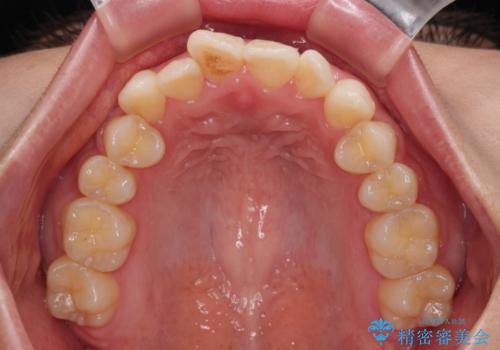

- 口元の突出感と口の閉じにくさを気にして来院された患者様です。

上下左右第一小臼歯4本を抜歯し、ワイヤー装置にて口元を引っ込めるよう矯正治療を行うこととしました。